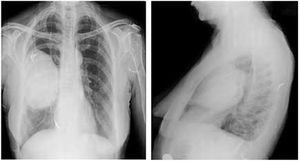

Case History: 2-year-old female with complains of difficulty breathing, paroxysmal coughing, and wheezing for one day.

Published: January 5th 2016 | Updated: